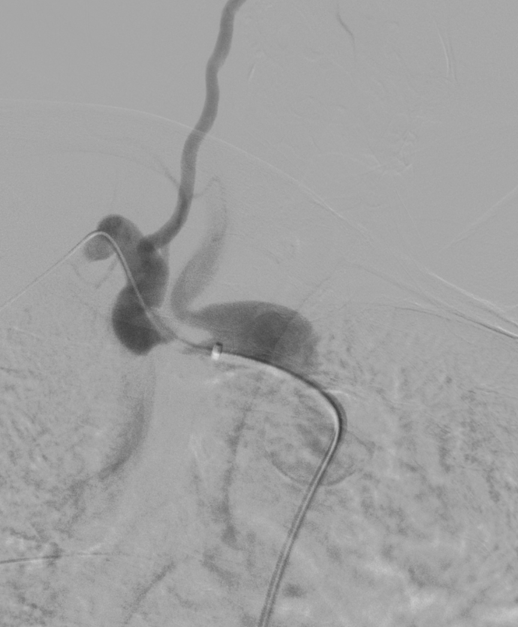

病例二

复杂的右锁骨下动脉闭塞病变:

对于闭塞病变,开通导丝的方向至关重要。根据CTA提示的特定角度(如 RAO 32° CRA 12°)进行投照,能为术者提供最清晰的路径导向,成功引导导丝通过闭塞段。

图:CTA提示 RAO 32  CRA 12

图:按RAO 32  CRA 12开通成功